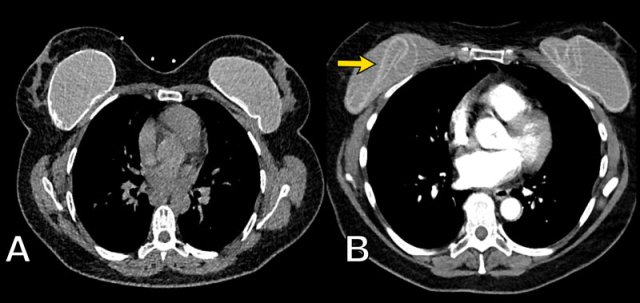

X-Ray and CT

Chest X-Rays and CT do not play a role in examining breast implants.

Sometimes they can be detected on X-rays for instance when there are capsular calcifications or when a filling valve of an expandable prosthesis is seen (arrow).

Also on CT sometimes complications can be seen, but usually CT does not give adequate information about the integrity of the prosthesis.

The chest film shows capsular calcifications in a medially displaced breast implant, which is not parallel to the breast contour.

The CT of the same patient shows also calcifications at the posterior side not following the contour of the implant indicating intracapsular rupture (arrow).

An intact implant has a homogeneous grey internal density on CT with a surrounding thin more hyperdens envelope and capsule.